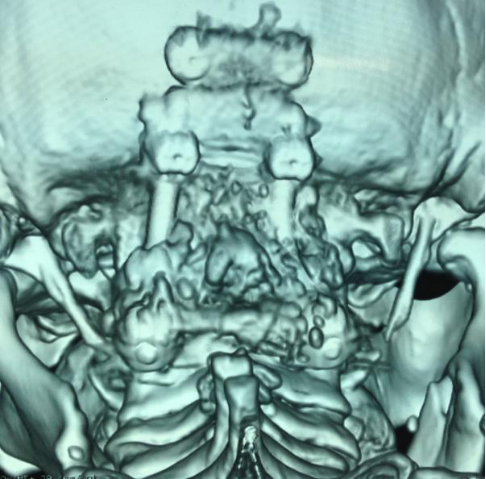

3影像学检查

手术前前屈位X光片寰枢椎脱位(寰齿前间隙7mm)。寰枢椎三维CT见寰枕融合,颅底陷入(齿状突位于钱氏线上14.2mm),右侧枢椎椎弓根发育狭小(小于2mm),磁共振显示小脑扁桃体下疝、颈髓损伤伴椎管狭窄。

4术前片子

全麻后,显微镜下行颈后路减压+枕颈撑开复位椎弓根侧块(左侧枕骨-C2~3,右侧枕骨-C3)螺钉钛棒内固定+植骨融合术。术中C臂下行枕颈撑开复位椎弓根侧块置钉。术后复查见椎管减压后脊髓位置良好,小脑扁桃体下疝改善,寰枢椎脱位复位。患者症状逐渐好转。